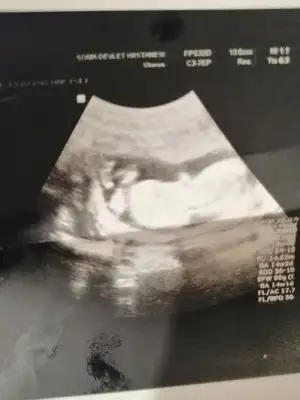

dr soylemeden siz gorun genital nub teorisi ( bebegin cinsiyeti)

banada bakarmısın çok merak ediyorum hemen alışveriş yapmak istiyorum:anneadayı::KK48:

• IMG_20210608_174953.webp

IMG_20210608_174953.webp

25,1 KB · Görüntüleme: 81